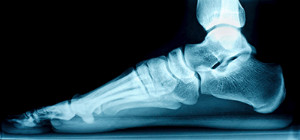

Foot Problems Caused by Diabetes Diabetics are at risk for many types of foot problems, the most common of which is nerve pain. High blood sugar levels can cause damage to the body’s peripheral nerves, and that includes those serving the feet. Another common cause of...

Reasons That Stress Fractures Can Develop Many people who are athletic suffer from stress fractures. The foot is a common place for this type of injury to occur, and it happens from gradually increasing speed and distance too quickly while running. Additionally, it...

Treatment Options for Turf Toe InjuryTurf toe is an injury that affects the base of the big toe, which is termed the first metatarsophalangeal, or MTP joint. It occurs from repeatedly overstretching that joint. This is a common injury among football or soccer players,...